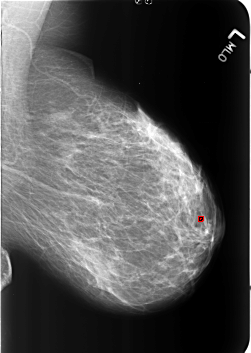

B_3213_1.RIGHT_MLO

LEFT_MLO LINES 5640 PIXELS_PER_LINE 4008 BITS_PER_PIXEL 12 RESOLUTION 50 OVERLAY

FILE: B_3213_1.LEFT_MLO.OVERLAY

TOTAL_ABNORMALITIES 1

ABNORMALITY 1

LESION_TYPE CALCIFICATION TYPE LUCENT_CENTER DISTRIBUTION N/A

ASSESSMENT 2

SUBTLETY 5

PATHOLOGY BENIGN_WITHOUT_CALLBACK